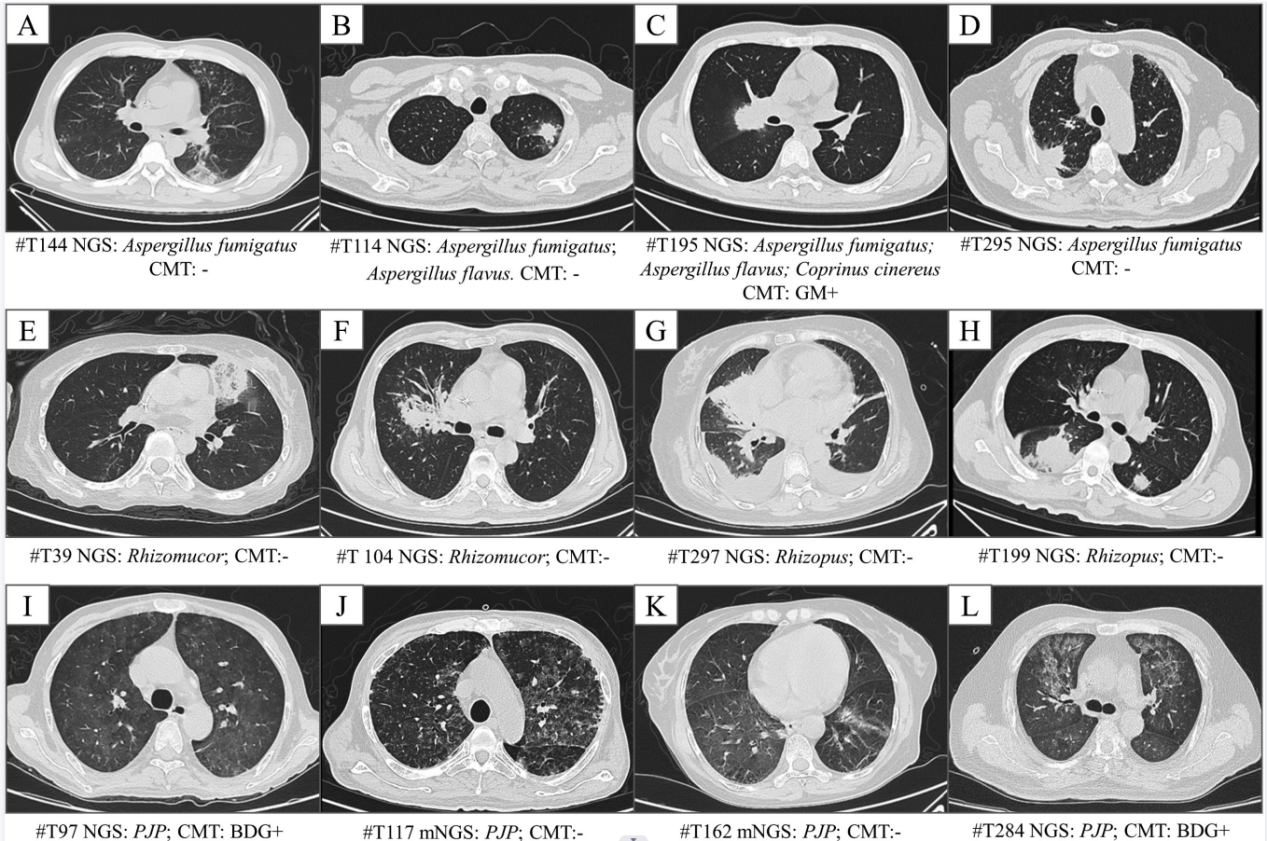

随后,研究者对血液样本病原mNGS检测在疑似肺部真菌感染患者中的诊断价值进行分析。结果显示,曲霉、毛霉、肺孢子菌这三种血液病患者肺部感染最常见的真菌病原,检出率分别为14.2%8.1%5.0%。其中粒缺患者曲霉检出率高于非粒缺患者,检出曲霉的23名患者中,传统微生物学检测仅检出10名患者。对检出真菌的46名患者,临床医生对其半数以上进行了药物调整,优化了抗真菌感染治疗策略。